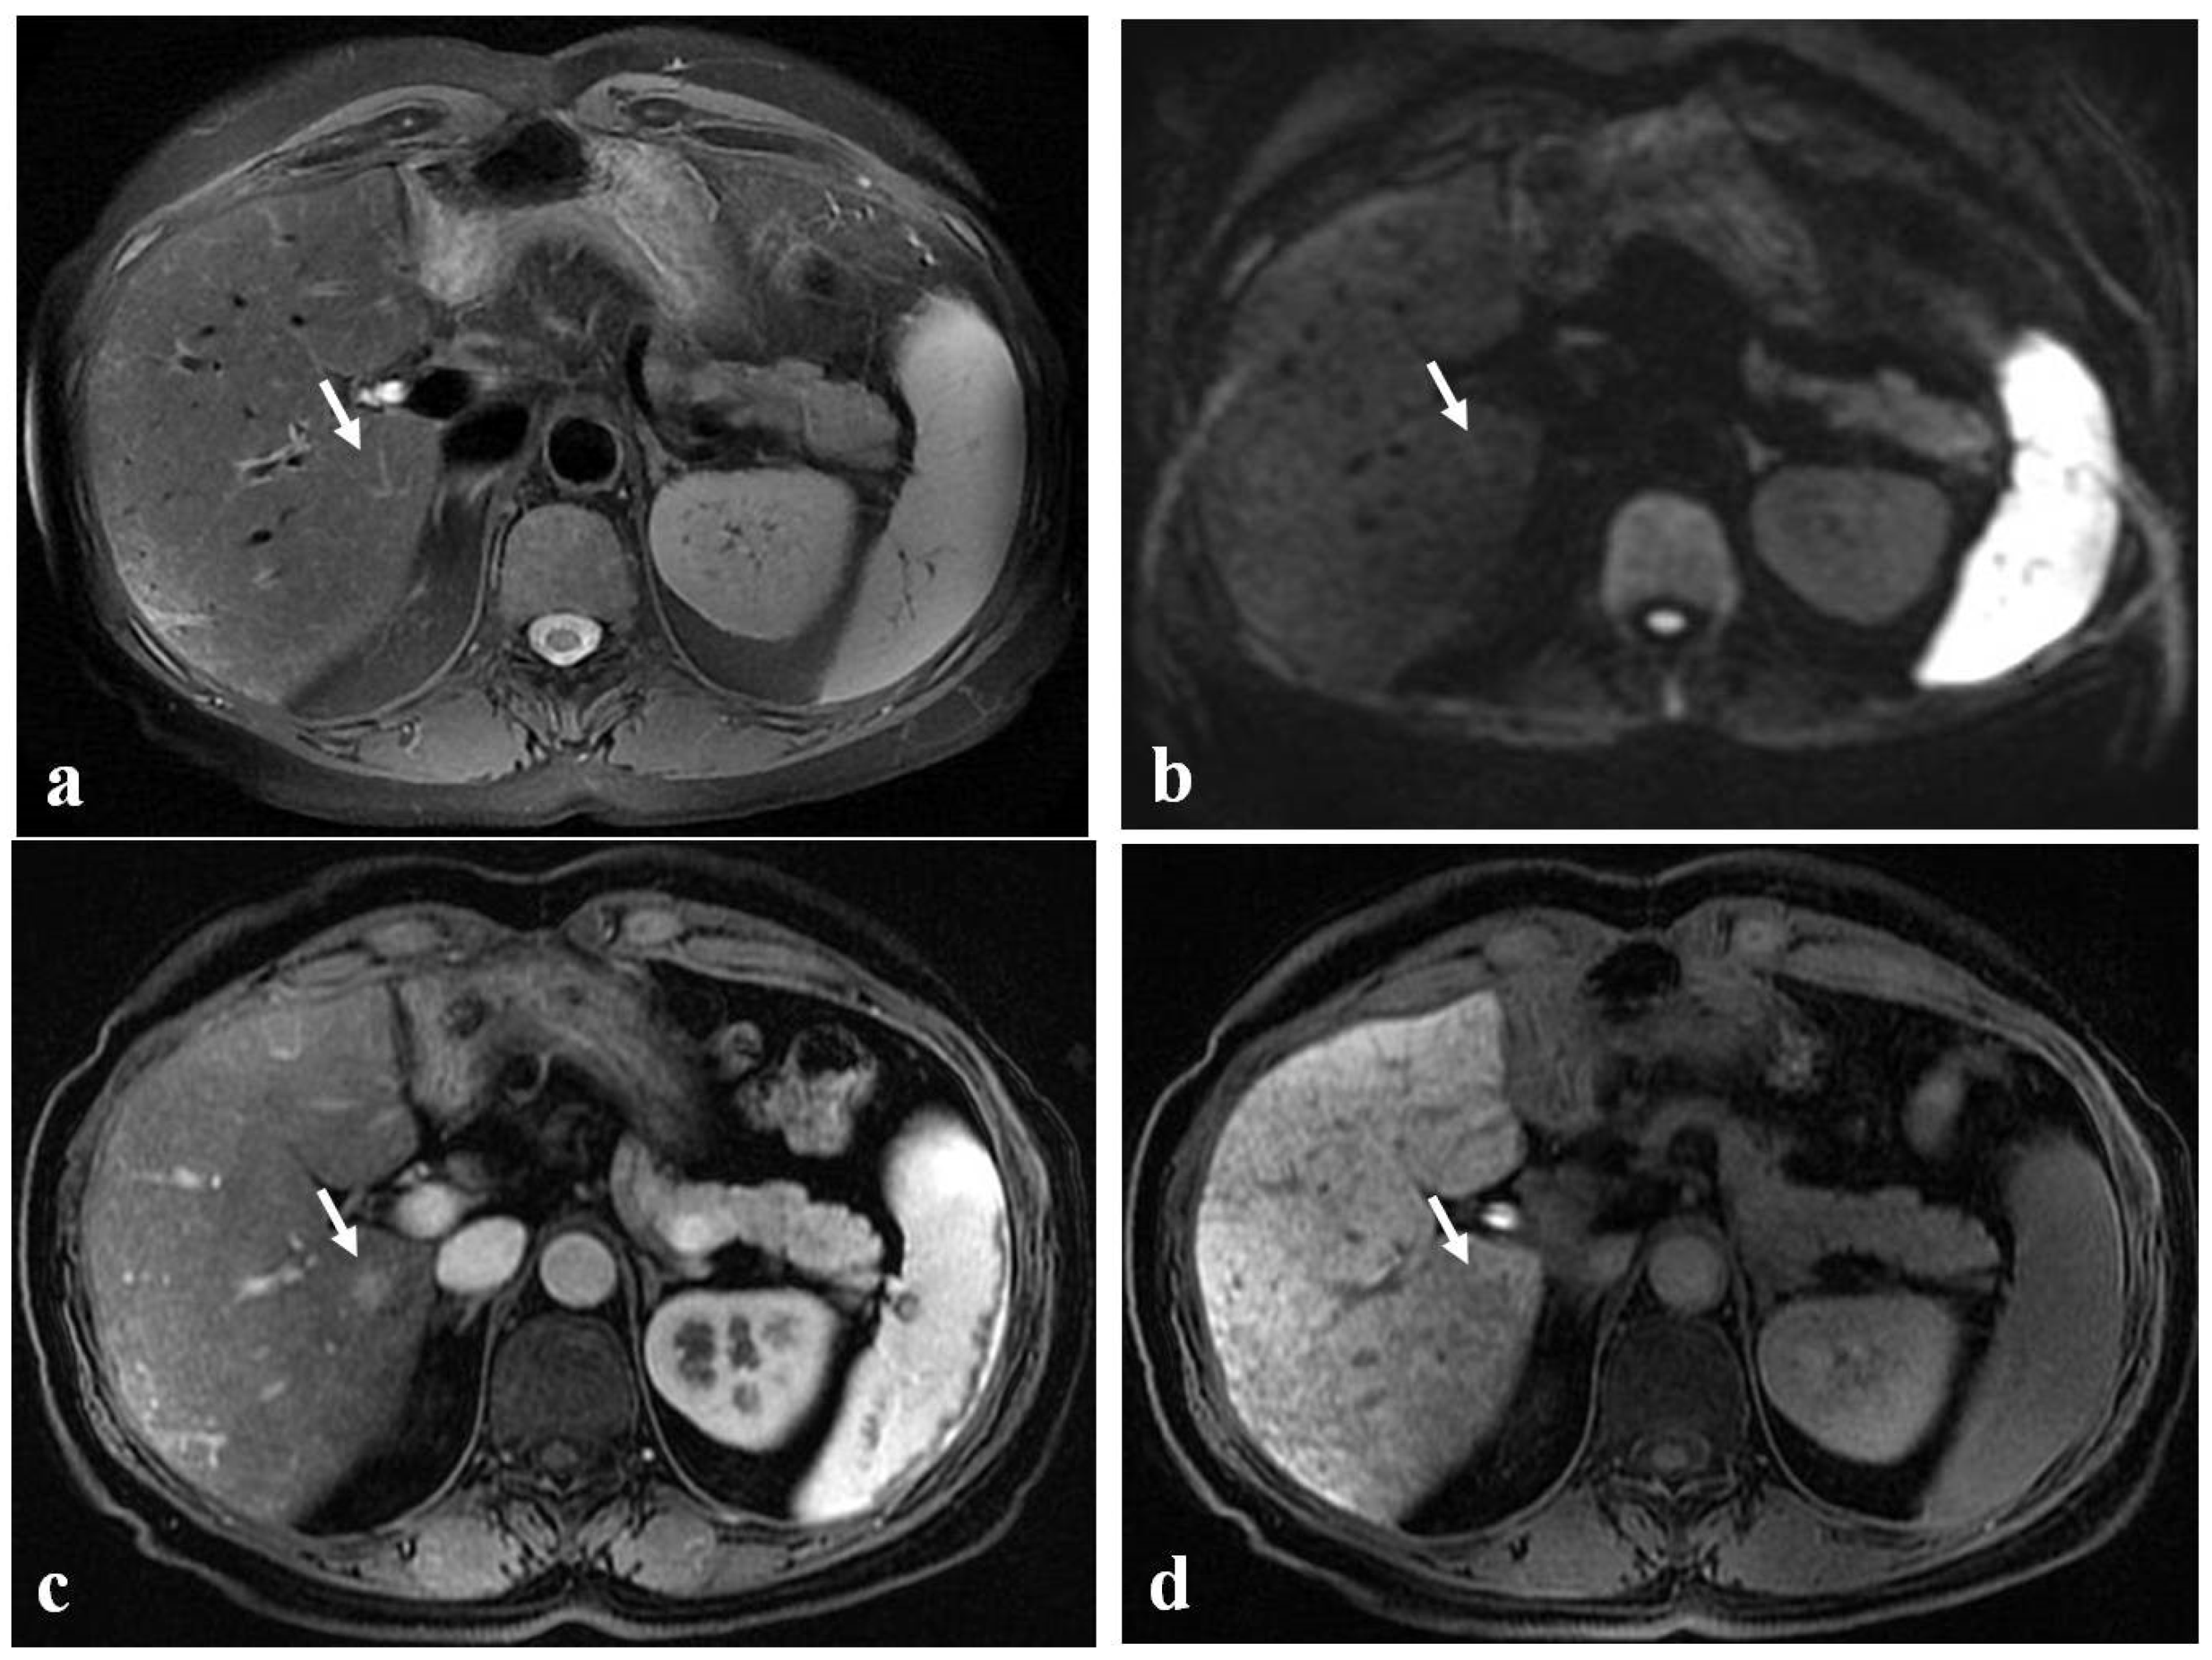

Figure 6.

(a–d) A 52-year-old woman with hepatic metastases from colon cancer undergoing neo-adjuvant chemotherapy with folinic acid, 5-fluorouracil, oxaliplatin, and irinotecan (FOLFOXIRI). After chemotherapy, a new centimetric lesion appeared in segment 7 (arrow). The lesion was not appreciable in the T2-weighted image (a) or in the DW-MRI image, with b-values of 1000 s/mm2 (b). After the administration of Gd-EOB-DTPA, the lesion appeared hyperintense in the arterial phase image (c) and slightly hypointense in the hepatobiliary phase image (d) and was not easily recognizable from the surrounding hepatic parenchyma, which is markedly inhomogeneous and suggestive of SOS. The findings are consistent with an NHR lesion.